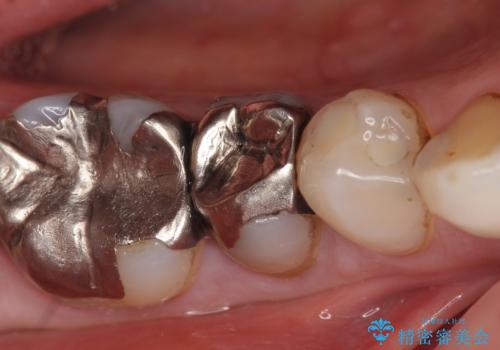

- 右下の歯でものを咬むと違和感があるので診て欲しいといらっしゃった方の症例です。

右下5番目の歯に根尖病変を認めたため、再根管治療を行い、オールセラミッククラウンによる補綴を行いました。

今回用いたオールセラミッククラウンは、ジルコニアフレームという白い素材の上にセラミックを盛っているため審美性が非常に高いのが特徴です。

またジルコニアは人工ダイヤモンドの材料にも使われているほど高い強度を持っており、そのためオールセラミッククラウンは審美性だけでなく、奥歯やブリッジの補綴も可能とするクラウンです。